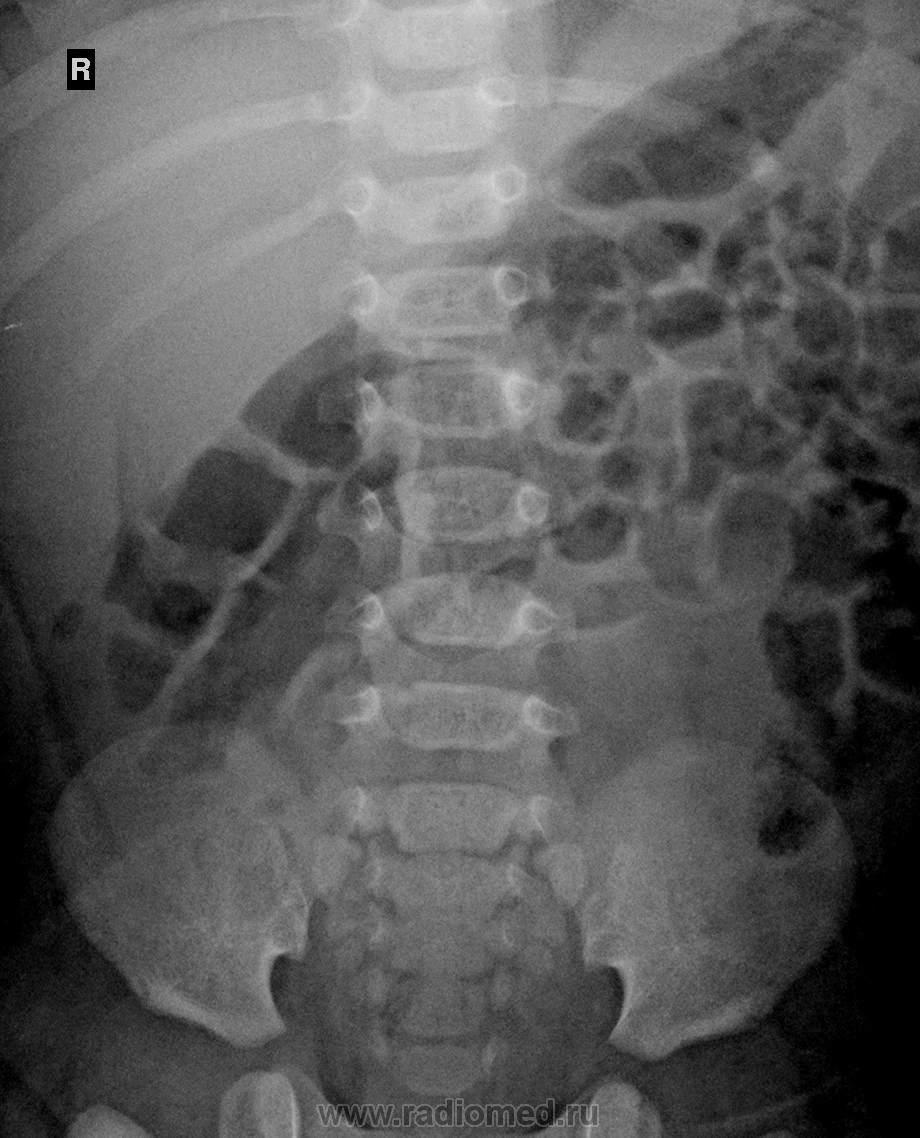

Вчера проводил экскреторную урографию 3х месячному ребёночку, по УЗИ гидронефроз правой почки, в анамнезе сильное беспокойство ребёнка, впринципе не впервые, но возник конфликт с дестким урологом, представляю вашему вниманию снимочки:

На представленных урограммах рентгенологическая картина несколько противоположная, определяется гидронефроз левой почки с дефектом наполнения рентген-контрастного вещества в пиело-уретральном сегменте и частично в/3 левого мочеточника. В правой почке тоже есть гидронефротическая трансформация, можно назвать прегидронефрозом, имеются множественные линейные дефекты рентген-контрастного вещества в мочеточнике.

Из проведенных в  стандартное время урограмм 5-10-15 минуты, для меня вся картина становится несколько понятной, имеет место быть вероятнее всего аномальный ход сосуда слева. Но возникает некоторая конфликтная ситуация с детским урологом, по поводу проведения отсроченной урограммы(в данном случае была проведена на 45 мин), он настаивает на отсроченной(обосновывая это стандартным алгоритмом ведения таких детей) я же настаиваю на своём.

Впринципе  снимок я сделал и ещё кое-что выявил,  наличие дивертикула мочевого пузыря. но картина впринципе осталась прежняя. У меня же есть вопрос к коллегам которые занимаются непосредственно детской урологией,  имеет ли смысл проведение отсроченной урограммы при наличие гидронефроза с контрастированием на всём протяжении мочеточника? Или это является подстроховка для проведения хирургического вмешательства? Или может я несколько не грамотно себя повёл?

Гибронефроз слева есть, есть эктазия справа. Мочеточник слева не виден, значит блок на уровне перехода лоханки в мочеточник. Может мочетосника  слева нет. Насчет дивертикула не уверена.

Мочеточник слева четко видно на уровне н/3, с/3 и частично в/3:

Уважаемый коллега V1tal! Мне сложно судить о пациентах 3-х месяцев от рождения. У взрослых- при такой картине считаю бесполезным проведение отсроченных снимков. Уже получена картина нарушения выделительной функции левой почки (аномальное отхождение сосуда). Можно сделать урограммы через 1 час, 2 часа - картина останется прежней. Есть нарушение эвакуации. Если пациент планируется на оперативное лечение, показана ретроградная уретеропиелография. Определяется уровень патологии. Соответственно ему - разрез и пластика. Справа у пациента то же не все благополучно. Почка ниже обычного. Расширена лоханка(хоть и внепочечного типа) и тоже аномальное отхождение сосуда. Только с меньшим нарушением выделительной функции.  Далее все решает лечащий доктор. Все зависит от его уровня квалификации и подготовки.

Все сказано уже. Гидронефроз и мегауретер слева уже можно ставить, справа пиелоэктазия. Обычно цистографию назначают при такой картинке, а в узко специализированной больнице урологи балуются пробой с лазиксом перед 3-м снимочком. В своей работе отсроченный снимок через час делаю, через 2 крайне редко.

Вы прежде всего консультант, коллега) Если клинициста настаивает, то по обоснованию в истории) провожу на 5, 10, 12 лежа 12 стоя, прошу покашлять) далее по функции выведения на 30. 60. 120. 180. Но! Если нужно) По серии урограмм че? "Двойка" участковым педиатрам! Недоглядели у крохи, и уже потеряли в декомпенсации слева все((( Если справа не решить вопрос в кротчайшие сроки, а рефлекторная регуляция гладкой мускулатуры лоханки уже в стадии декомпенсации...( ВПР МВС: множественные врожденые стриктуры обоих мочеточников. Или может Вы коллега не разобрались во входящей документации, гляньте пожалуйста ранее проводимые УЗИ МВС? За три месяца ни как не должно потеряться...

Делаем, при необходимости, отсроченные через 1, 3 и 6 часов, до начала опорожнения. Наши детские урологи уверяют, что это им важно для определения дальнейшей тактики лечения - если при небольшой степени гидронефротической трансформации контраст "висит" в почке до 6 часов - тогда операция, если уходит быстро, тогда можно подождать, пока подрастет ребенок.

В предоставленном случае весьма вероятно сочетание с ПМР, потому что мочеточники широковаты, однако явной их обструкции не видно, разве что справа чуть-чуть.